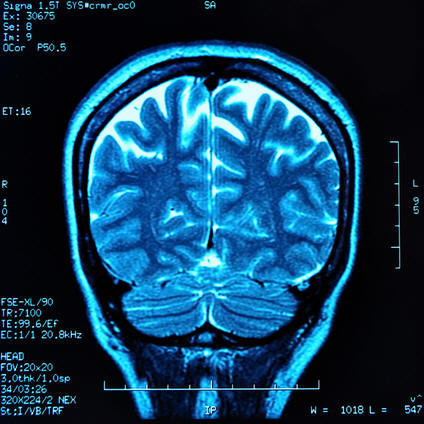

Томограмма головного мозга

Магнитно-резонансный томограф (МРТ), ядерно магнитно-резонансный томограф (ЯМРТ) или магнитно-резонансная томография (МРТ), является основным инструментом медицинской техники для создания изображений, используемых в радиологии для подробной визуализации внутренних структур и органов человека. Томограф обеспечивает хороший контраст между различными мягкими тканями тела, что делает его особенно полезным при исследованиях мозга, мышц, сердца и диагностики рака по сравнению с другими медицинскими методами визуализации, такими, как рентгеновская компьютерная томография (КТ) или рентгенография.

В отличие от рентгеновского обследования ЯМР-метод абсолютно безвреден и гарантирует намного лучший контраст между разными типами тканей, что позволяет легко различать здоровые и пораженные участки. ЯМР-томография особенно успешно применяется при диагностике патологий центральной нервной системы и костно-мышечного аппарата, а также для распознавания опухолей на фоне здоровых тканей.